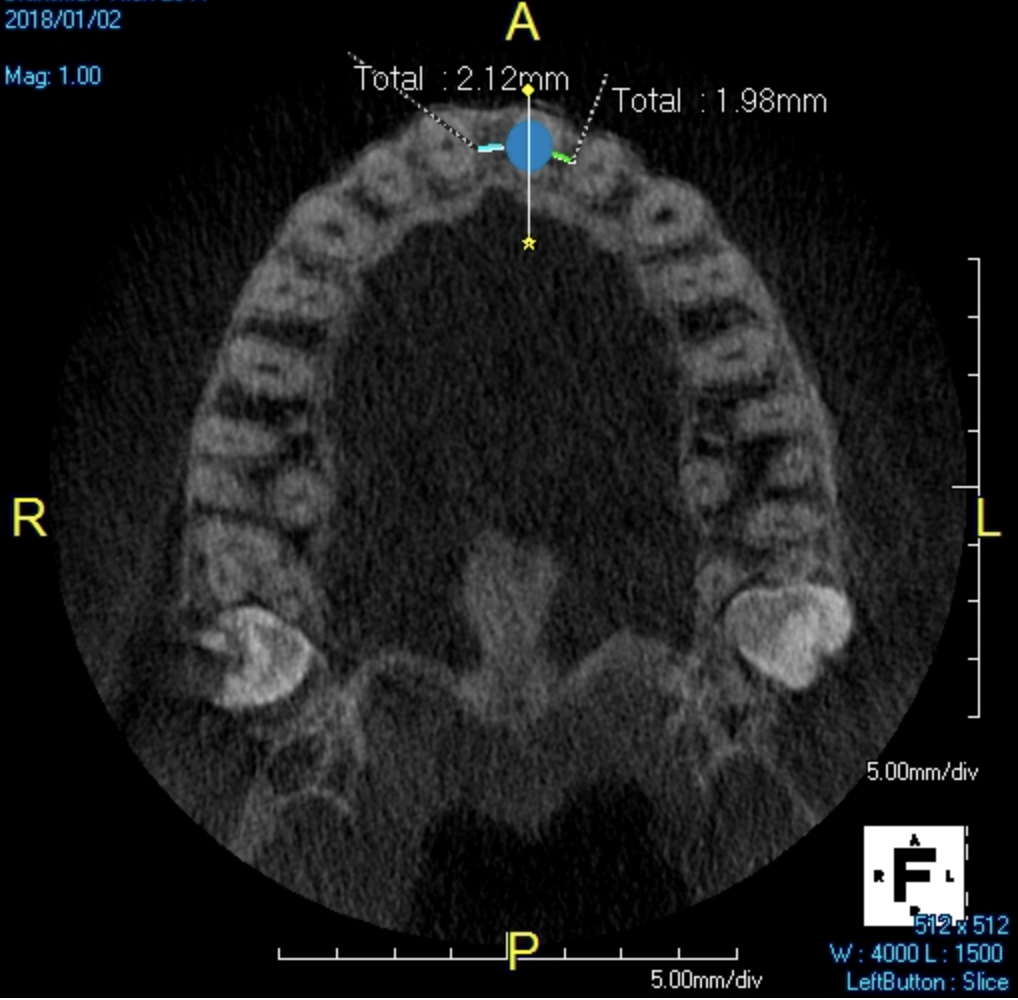

A young man presented with a fractured maxillary left-central incisor on a Monday morning after a Saturday evening discussion that did not end well (Figure 1). Visual oral examination and palpation of the structures revealed mobility of 3+, pain on palpation and percussion, a thick soft-tissue profile, and a low lip line. Gingival zeniths were irregular, there was a class II division 2 deep bite, and the periodontium was healthy overall (Figure 2 through Figure 4). Radiographs requested at the time of the initial visit were periapicals, panoramic, and CBCT images (Figure 5 and Figure 6). After all images and information were reviewed and the extent of his injury was discussed, the patient was presented with the following options: removable prosthetics, fixed partial denture, extract and do nothing, or extract and place a dental implant with bone augmentation.

Reviewing the CBCT images with the patient proved beneficial because he was able to clearly see the complete fracture of his tooth in the apical third of the root (Figure 6). Figure 5 represented what is a common radiograph in most dental offices, but it was not clear enough to diagnose a root fracture of this nature. The patient understood that the prognosis was poor and that the long-term restoration he wanted would mimic nature and be maintainable like natural dentition. The visual examination and photographs provided a basis for subsequent dental therapy and a definitive treatment plan for the future. The patient decided to move forward with tooth extraction, grafting, and immediate dental-implant placement with a screw-retained provisional out of occlusion.

Due to the young man's college schedule and consequent time constraints, he was appointed the next day. A surgical guide was not used because there was limited time and there was an appropriate amount of thick soft-tissue profile, measured amount of bone volume based on the CBCT, and virtual placement of the dental implant. Figure 7 and Figure 8 showed the measurements to be more than 2 mm buccal and lingual to the proposed implant placement. The interproximal dimensions mesial and distal to the implant proposal were greater than the 1.5 mm previously mentioned in this article. The CBCT images provided the spatial dimensions and a mental awareness regarding implant placement angulation. The final position was predetermined and acceptable for the considerations necessary in choosing the abutment (zirconia or titanium) and final restoration. Because the implant had appropriate bone length and abundant 360-degree bone volume, minimal augmentation was needed. The natural clinical crown was used to provide an ideal emergence profile to enhance the soft-tissue architecture. Atraumatic tooth extraction was extremely helpful in the development of this treatment plan. Having 1.5 mm to 2 mm of facial bone available after the extraction would facilitate exceptional healing and long-term results. Figure 9, occlusal view, depicted a thick soft-tissue profile and properly placed implant within the arch form.

Fig 1. CBCT image (preoperative).

Figure 1